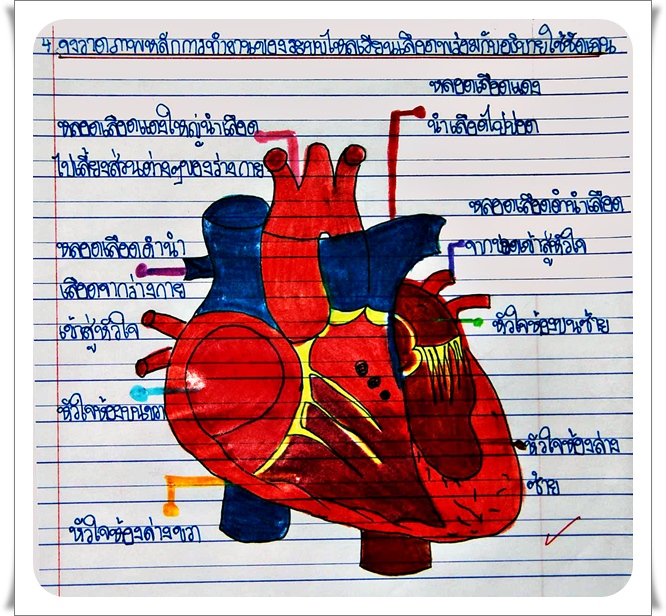

ระบบไหลเวียนโลหิต ทำหน้าที่อะไร และมีส่วนประกอบสำคัญอะไรบ้าง

หัวใจกับการไหลเวียนของเลือด – ระบบไหลเวียนโลหิต ม.2 ระบบหมุนเวียนเลือด | Science – Quizizz

ม.2 ระบบหมุนเวียนเลือด | Science – Quizizz ระบบไหลเวียนเลือด: หัวใจ

ระบบไหลเวียนเลือด: หัวใจ รูปภาพประกอบระบบไหลเวียนโลหิตของร่างกายที่วาดด้วยมือ PNG , ร่างกาย …

ระบบไหลเวียนโลหิตของมนุษย์ในระบบไหลเวียนโลหิต, สุขภาพ, ร่างกาย, หัวใจ … LOWER SECONDARY SARASAS WITAED RANGSIT: ผลงานนักเรียน วิชา วิทยาศาสตร์ …

LOWER SECONDARY SARASAS WITAED RANGSIT: ผลงานนักเรียน วิชา วิทยาศาสตร์ … ระบบหมุนเวียนโลหิต | TruePlookpanya